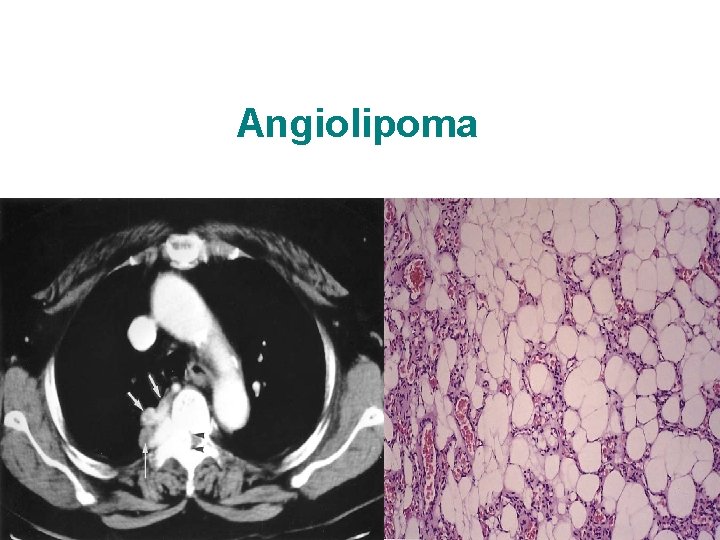

Angiolipoma

Mediastinal Mesenchymal tumours Benign Lipoma Hemangioma Lymphangioma Cystic hygroma Malignant Liposarcoma Leiomyosarcoma Rhabdomyosarcoma Hemangiosarcoma